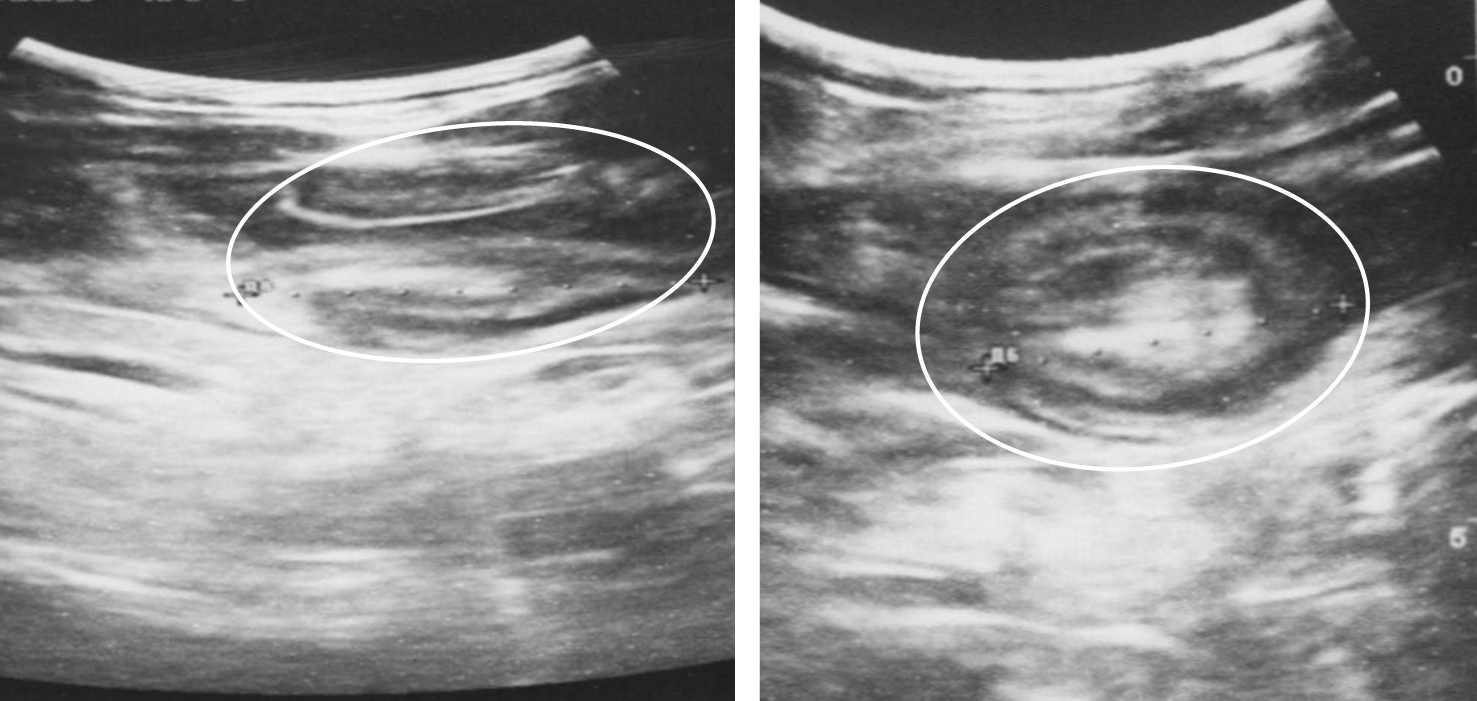

Диагностическая ценность, чувствительность и специфичность методов диагностики ООТК в экстренной ситуации и при плановом обследовании различны [11, 12]. Обзорная рентгенография позволила выявить свободный газ в брюшной полости у 10 из 12 пациентов (83,3 %) с перфорациями тонкой кишки и перитонитом. Еще у двух больных прикрытые перфорации были выявлены во время лапаротомии. Ультразвуковое исследование на фоне кишечной непроходимости (n = 51) позволило выявить ОТК у 20 пациентов (39,2 %), при этом у 17 пациентов (33,3 %) в стенке кишки были визуализированы гипоэхогенные, однородные, преимущественно внутриполостные структуры с ее утолщением и деформацией (рис. 2), признаки инвагинации у 3 (5,9 %) (рис. 3). У 31 пациента ОТК как причина ОКН выявлена не была (60,8 %).

Рис. 2. Гетерогенные внутрипросветные структуры неправильной формы на фоне расширенных петель тонкой кишки (выделены белым контуром)

Рис. 3. Ультразвуковая картина инвагинации, инвагинат отмечен белым контуром